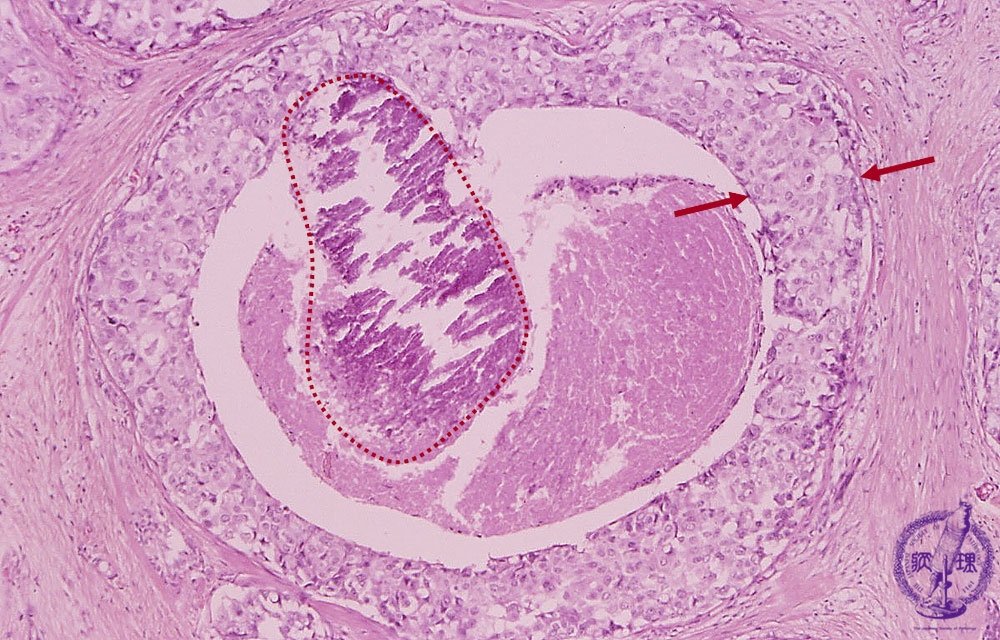

- ★(5)noninvasive carcinoma (comedo type)

Microscopic image(HE stain, high power view):Large carcinoma cells piled up to several layers filling ductal lumen (arrow). Central necrosis and necrotic calcification (dotted line) are also apparant.